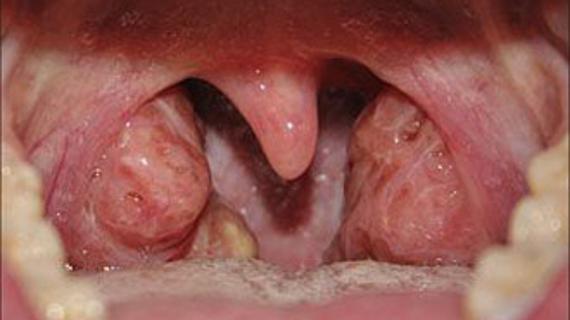

Заболевания горла